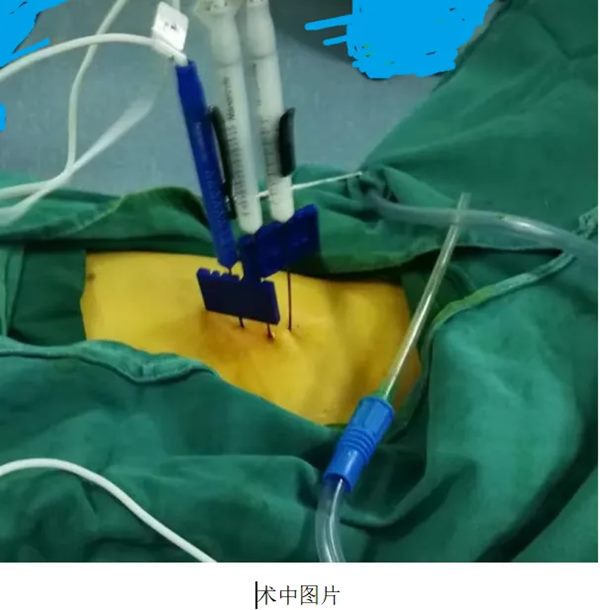

2024年12月,在手术部•麻醉科胡强夫主任麻醉团队及手术室刘丹丹护士长护理团队的配合下,在超声影像科杨青主任团队精准的超声引导下,李晓勇教授、陈升阳医生团队为患者实施超声引导下经皮胰腺癌纳米刀消融术。术后皮肤仅有数个穿刺针眼。经过林磊护士长团队精心护理,患者恢复顺利出院,治疗后腹痛完全缓解,饮食恢复至正常,肿瘤标志物降至正常。目前已完成术后第1疗程化疗治疗。